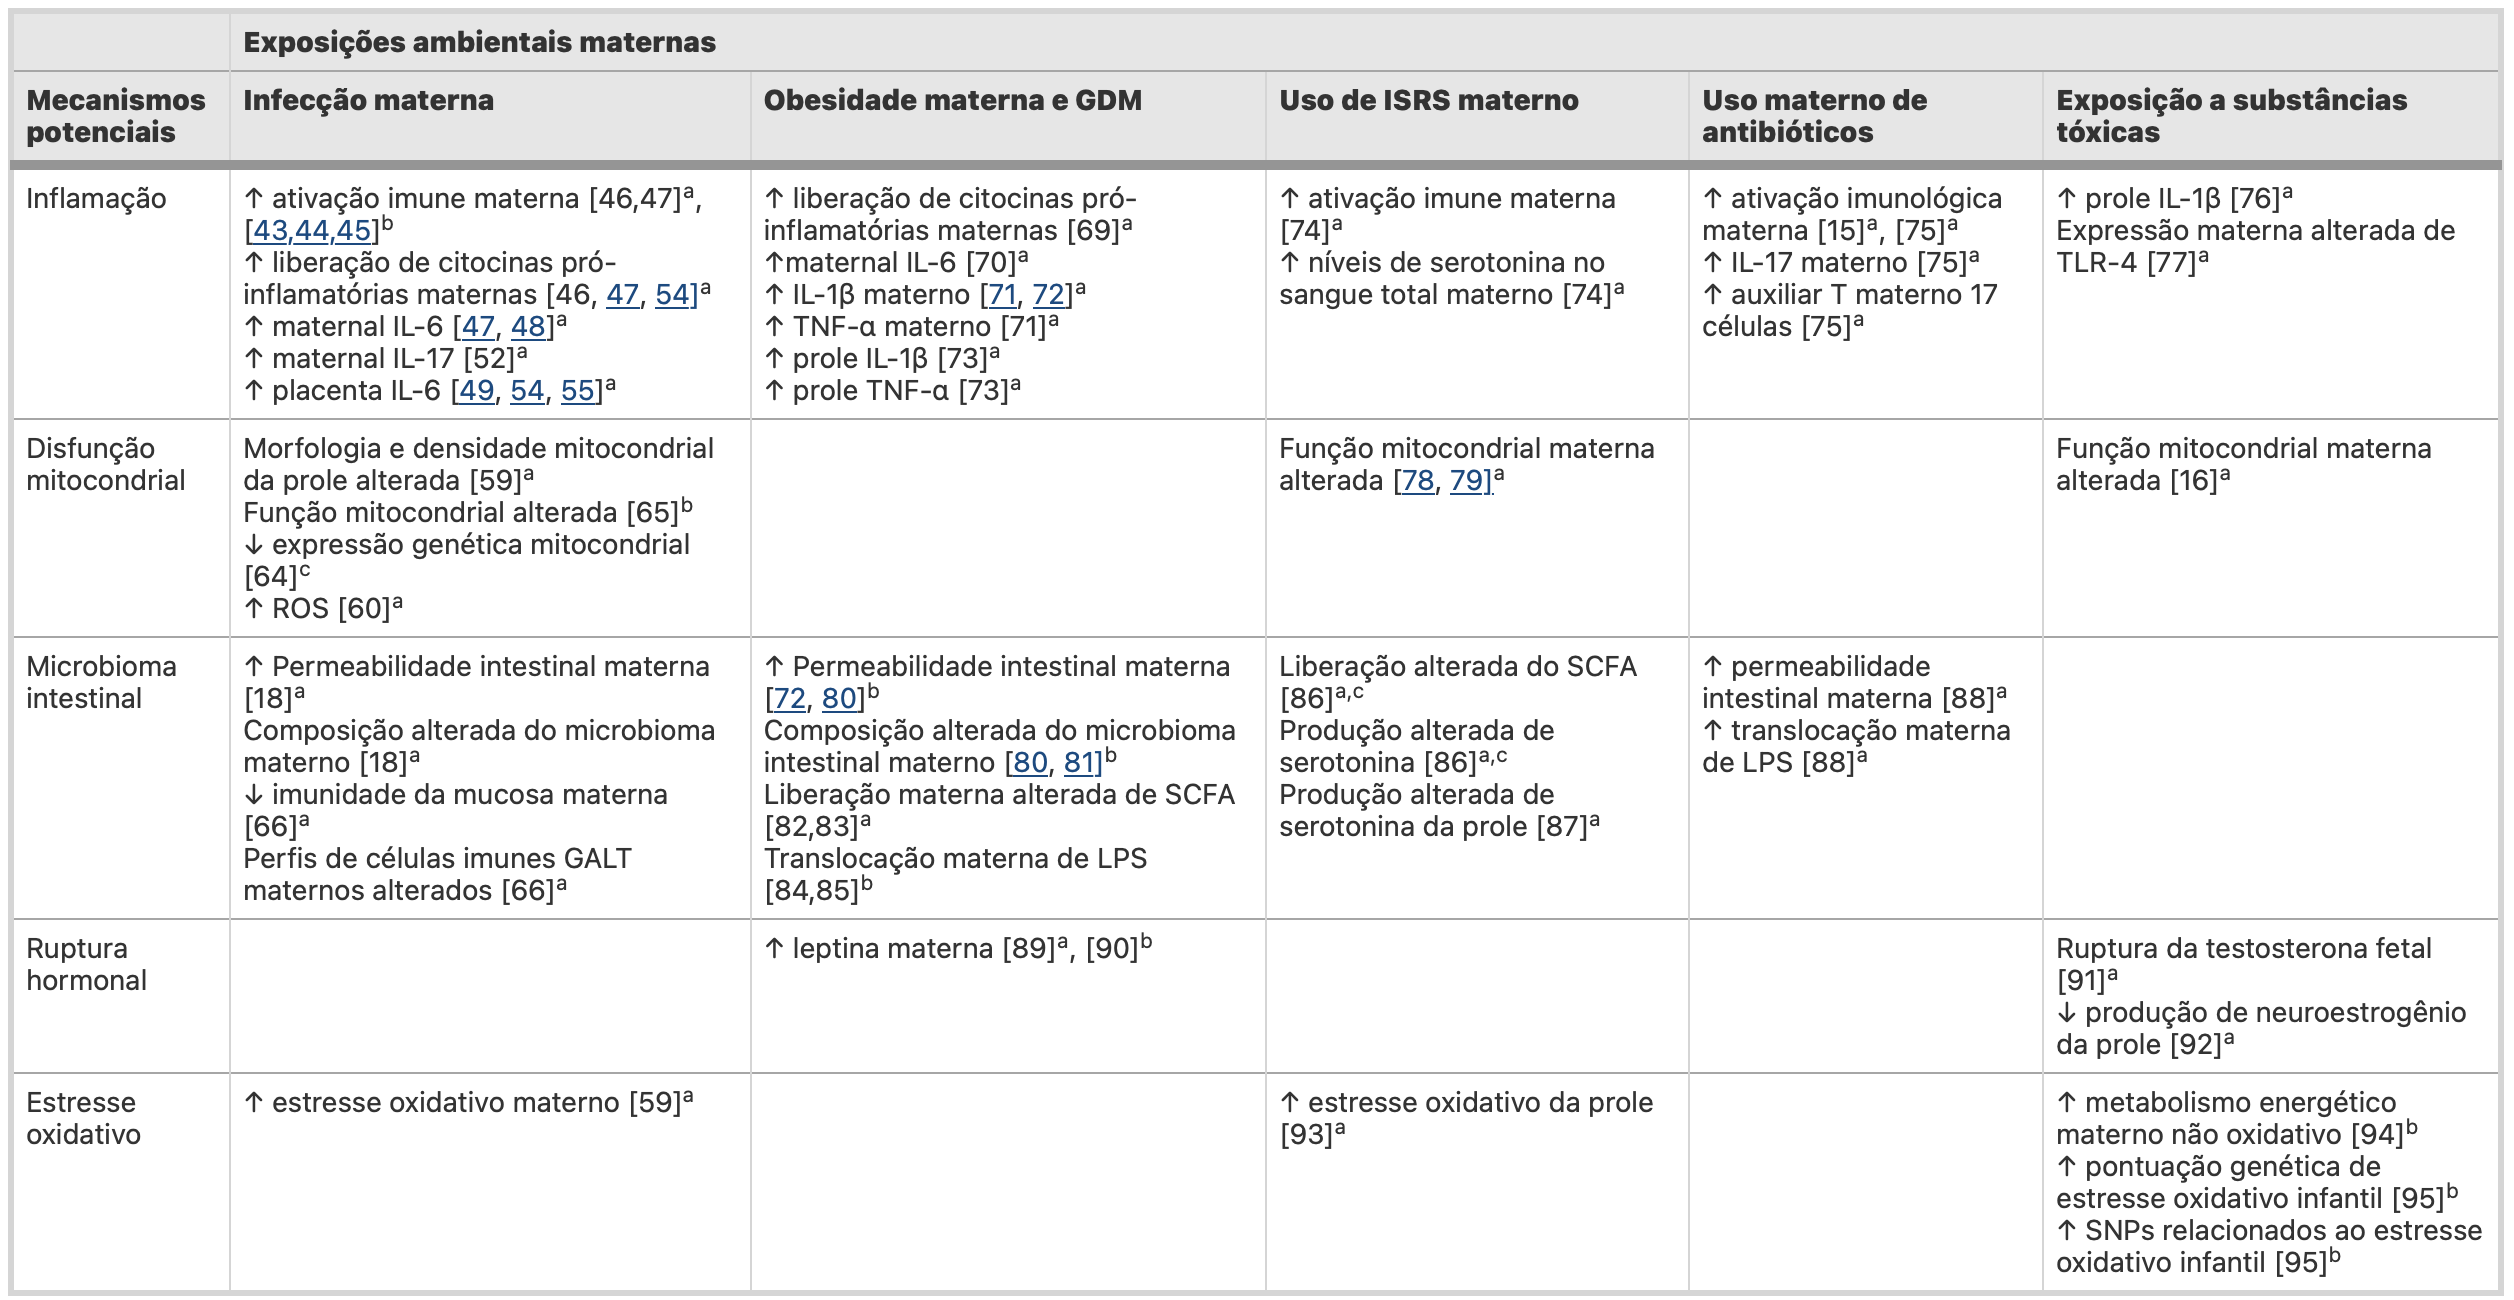

Resumo dos principais estudos de fatores de risco ambiental materno para TEA e mecanismos subjacentes.

GALT Tecido linfóide associado ao intestino, IL interleucina, LPS lipopolissacarídeo, ROS espécies reativas de oxigênio, SCFA ácido graxo de cadeia curta, SNPs polimorfismos de nucleotídeo único, TLR receptor toll-like, TNF fator de necrose tumoral

(a) Indica estudos com animais

(b) Indica estudos humanos

(c) Indica estudos in vitro